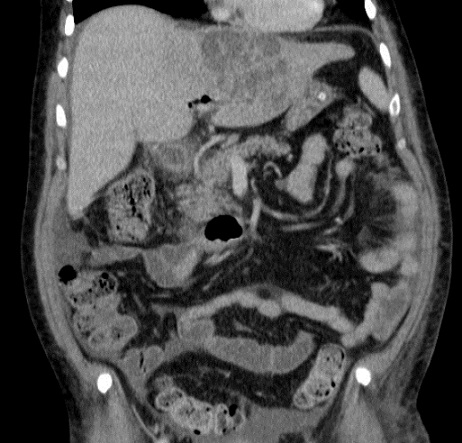

Image TDM d'une abces du foie en coupe

coronale . Aspect de la lesion est hypodense

multi loculaire se situe au foie gauche . Image

radiologique TDM encoupe coronal , aspect

radiologique en susgeste du abces a pyogenes |